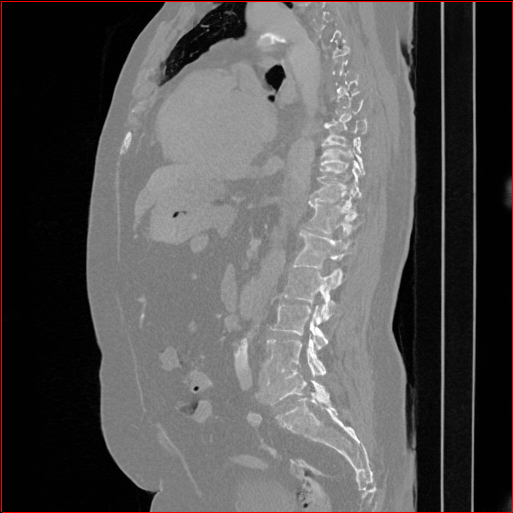

Figure 2: Qualitative comparison across axial (top row), sagittal (middle row), and coronal (bottom row) views. Columns correspond to different methods. MAISI-DDPM and MAISI-v2 in this figure are unconditional synthesis which do not use ControlNet or segmentation maps.

Qualitative Evaluation:

Figure 2 presents representative slices from the axial, sagittal, and coronal planes. GenerateCT (hamamci2024generatect) is a 2D model, so it lacks inter-slice consistency, leading to poor image quality in the sagittal and coronal views. MedSyn (xu2024medsyn) produces noticeably blurry results with mosaic-like artifacts, such as region inside the red box. HA-GAN (sun2022hierarchical) generates visually sharp images but with mosaic-like artifacts, such as region inside the red box. Also, its voxel spacing is not available, which limits its applicability in real-world medical imaging tasks. Moreover, all three methods are restricted to synthesizing small anatomical regions. In contrast, both MAISI and MAISI-v2 are capable of generating high-quality 3D volumes that span larger body regions while preserving fine anatomical details and realistic structure.